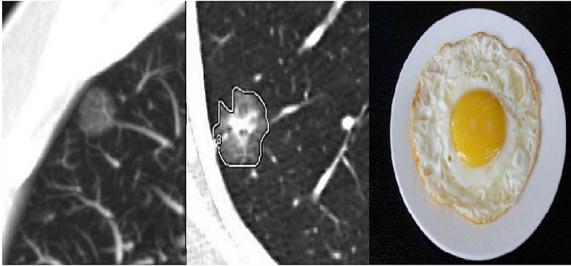

具有磨玻璃影特征的肺结节称为“肺磨玻璃结节”。肺磨玻璃影(GGO,ground glass opacity)在胸部CT表现为密度轻度增高的云雾状淡薄影 / 圆形结节,密度像磨砂玻璃或者云朵的一样,所以叫磨玻璃影。(如下图红箭头所示)

图一 肺磨玻璃影

单纯性或者完全性GGO是指病灶内无实性成分的病灶,在影像学上表现为完全的均匀的云雾状结节。而混合性GGO则是含有部分实性组织成分的病灶,类似“荷包蛋状”。

图二 单纯性与混合性GGO影像学表现对比